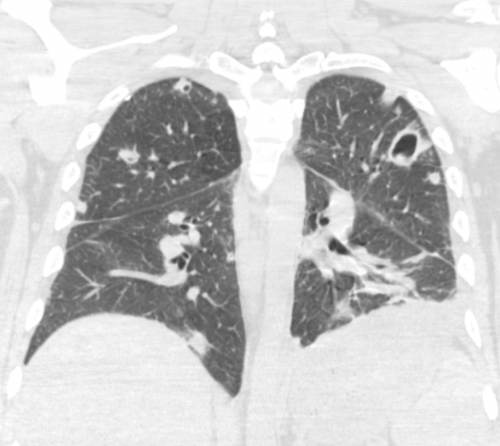

Age: 43

Sex: Male

Indication: Sepsis

Sample ReportMultiple bilateral pulmonary nodular opacities, several of which demonstrate central cavitation. In this patient with reported sepsis, the primary consideration is septic embolic disease. Consider chest CT and/or echocardiography for further evaluation. Recommend imaging followup to resolution to exclude underlying malignancy.

Small left pleural effusion with overlying atelectasis and/or airspace disease related to aspiration or pneumonia.